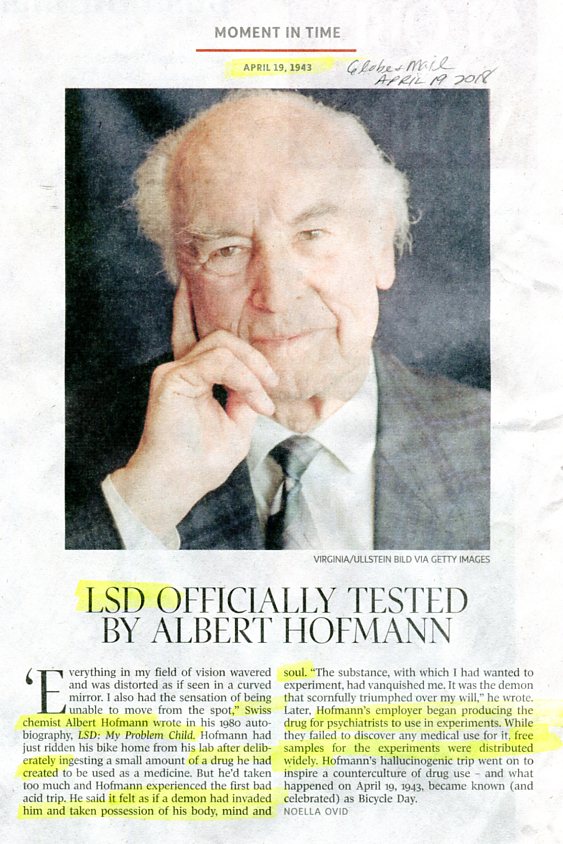

LSD officialy tested by chemist creator in 1943

(demon invaded & took possession of body/mind/soul)

GlobeMail, Apr 19, 1943-2018

ORWELLIAN WAR BY DRUGS &

5.Big Brother Pyramidal NWO & 32.BB Brotherhood